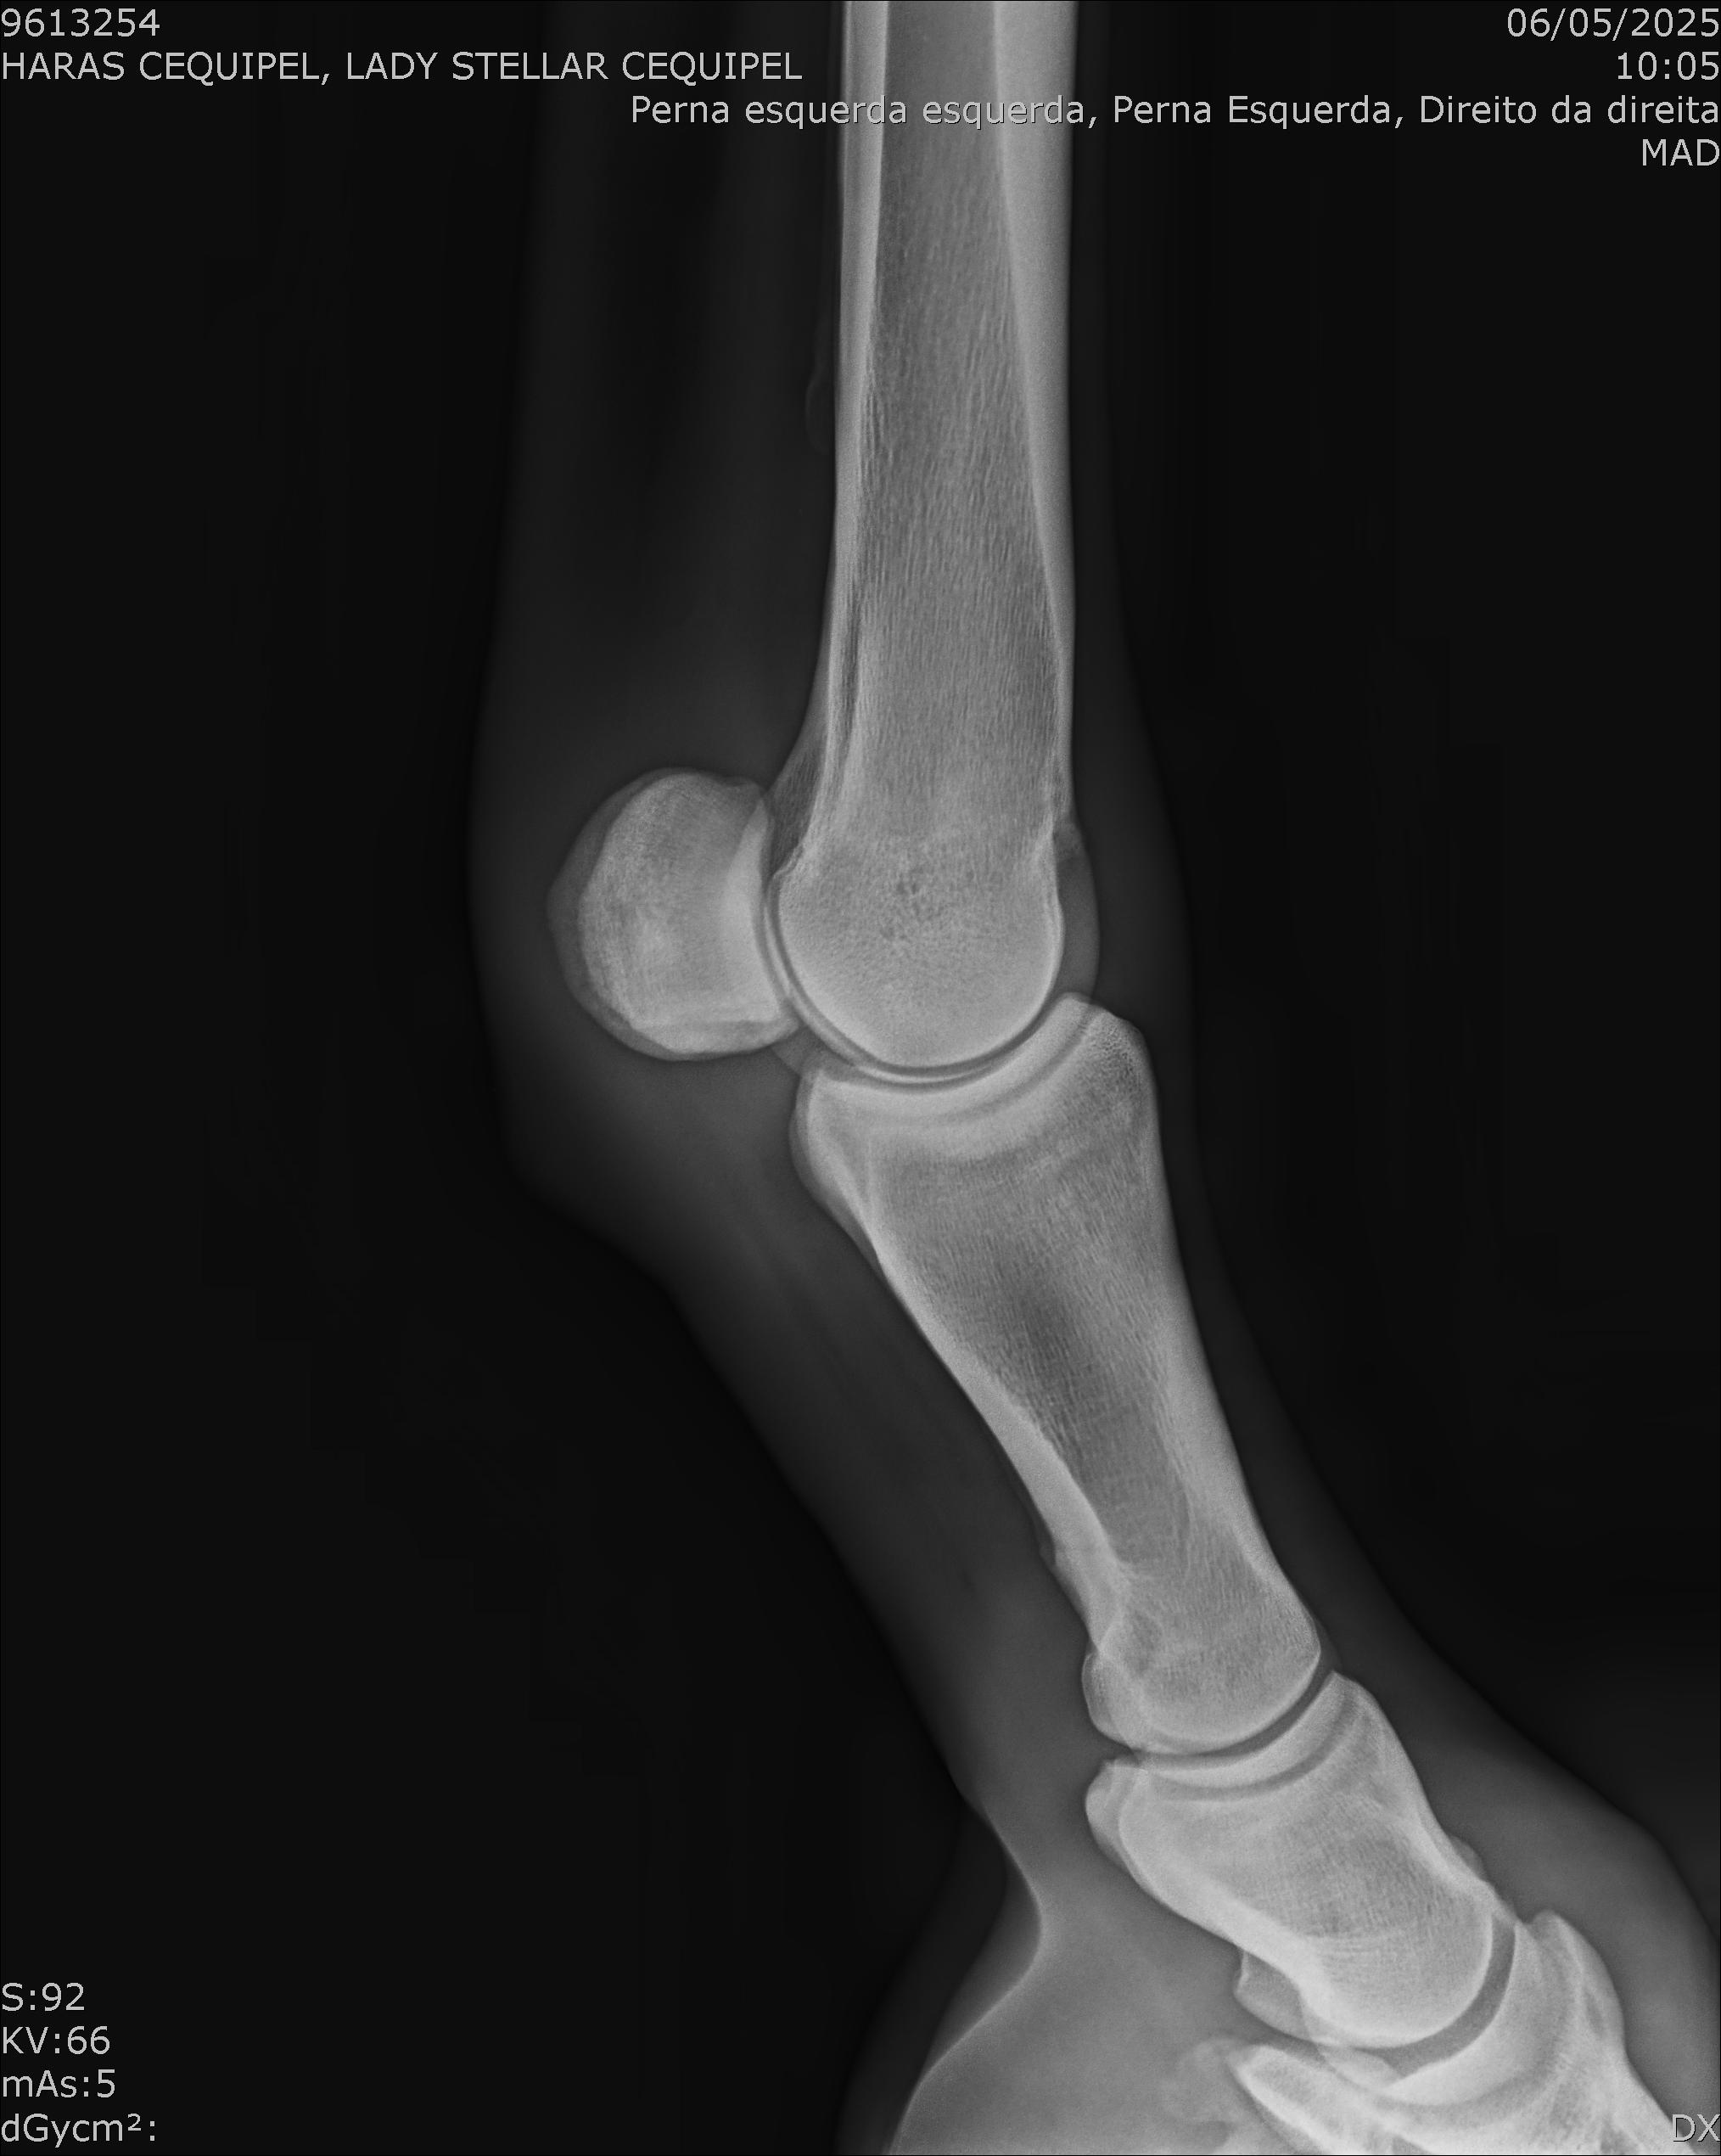

:: RAIOS-X DO LOTE